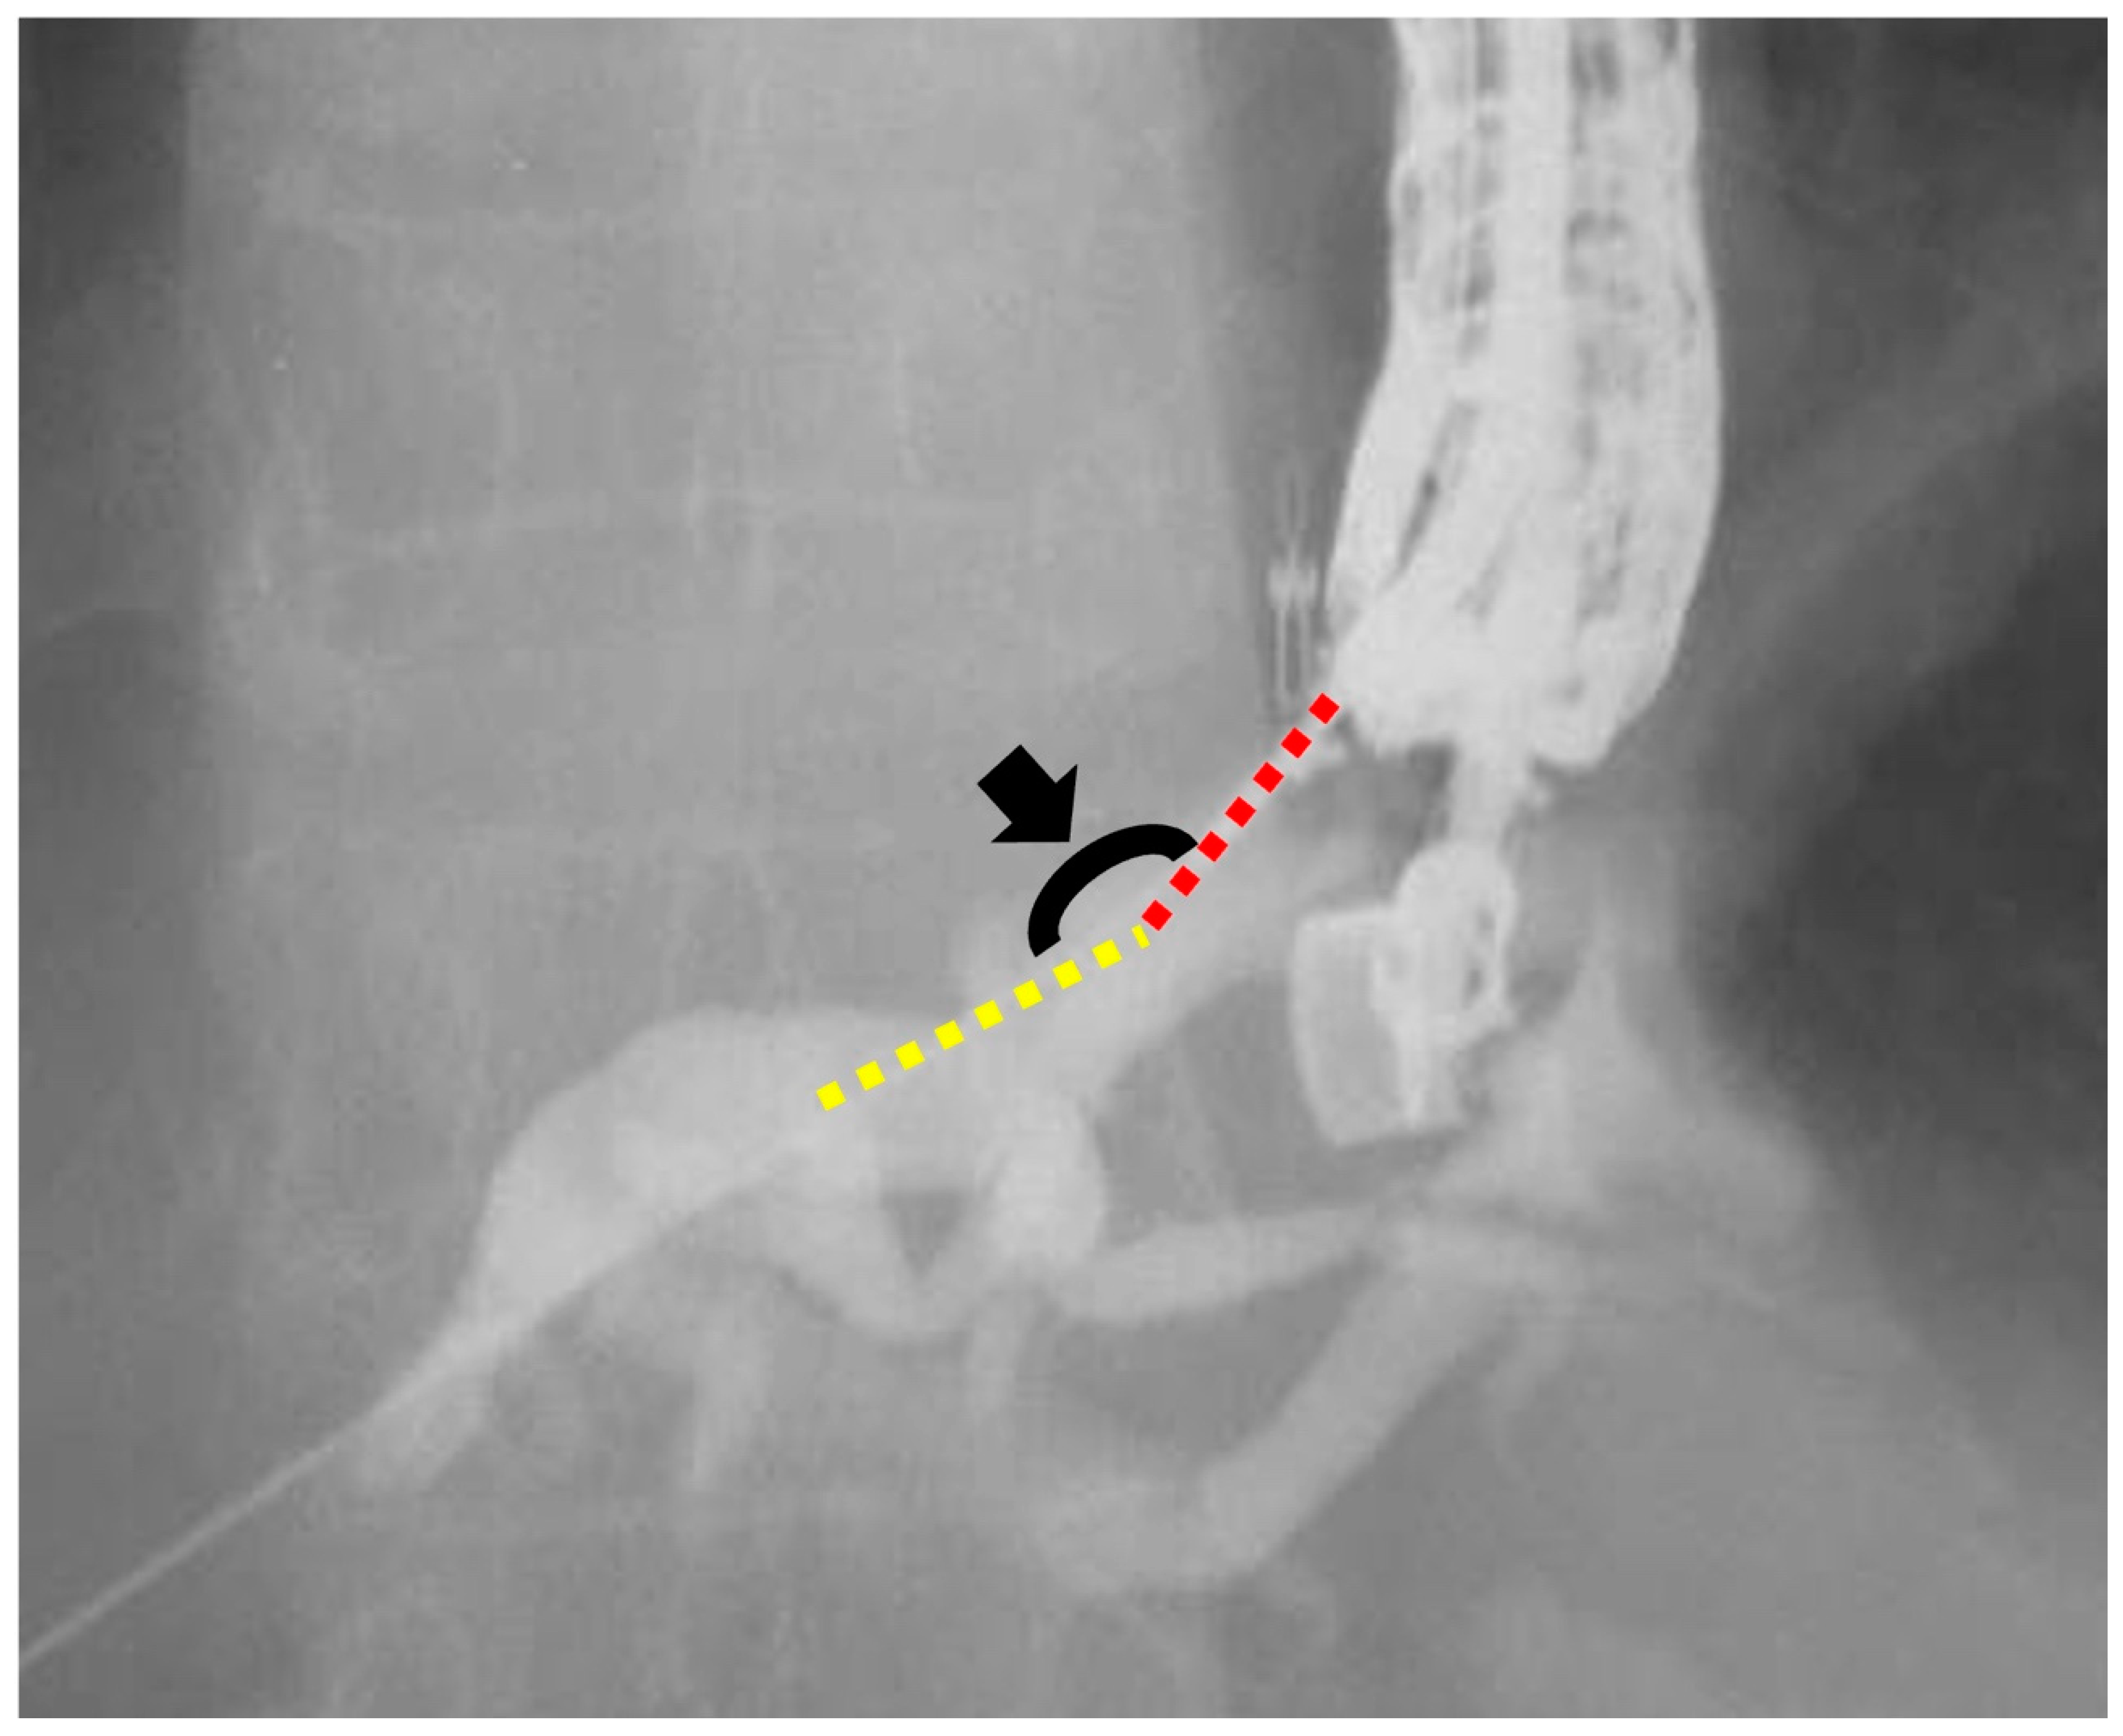

Figure 2.

Measurement of the insertion angle. The insertion angle (black arrowhead) is defined as the angle between the guidewire in the liver parenchyma (yellow dotted line) and the punctured peripheral intrahepatic bile duct (red dotted line).

We defined the conventional and novel groups as patients who underwent EUS-HGS using a conventional ERCP contrast catheter (MTW Endoskopie) or the novel ERCP contrast catheter (SHOREN), respectively. Patient data were collected from the electronic medical records and endoscopy databases. We compared outcomes between the conventional and novel groups. The primary outcome was the success rate of ERCP contrast catheter insertion in a single attempt. Secondary outcomes were the failure rate of ERCP contrast catheter insertion, insertion guidewire angle, overall technical success rate, procedure time, and AEs. These outcomes were compared between the two groups. Successful ERCP contrast catheter insertion was defined as the successful insertion of the ERCP contrast catheter into the intrahepatic duct. Successful ERCP contrast catheter insertion in a single attempt was defined as successful on the first attempt. If we pulled the ERCP catheter after the first attempt of catheter insertion or adjusted the scope position, ERCP catheter insertion in a single attempt was considered a failure. The insertion angle was defined as the angle between the guidewire in the liver parenchyma and the peripheral intrahepatic bile duct that was punctured (Figure 2). The overall technical success was defined as stent deployment in the intended position. The procedure time was measured from endoscope insertion to stent deployment. The AEs were defined and graded according to the American Society for Gastrointestinal Endoscopy Severity Grading system [13]. Bile peritonitis was diagnosed on the basis of ultrasonography or computed tomography findings and was defined as the presence of fluid collection after EUS-HGS, in addition to symptoms of infection, such as elevated infection markers on blood tests. Fever was defined as a fever of >38 °C persisting for 24 h after the EUS-HGS procedure. Abdominal pain was defined as new-onset abdominal pain that worsened after the EUS-HGS procedure.

The study outcomes are presented in Table 3. The success rates of ERCP catheter insertion in a single attempt were 80.8% (21/26) in the conventional group and 96.5% (21/22) in the novel group. The median guidewire angles were 114° and 90° in the conventional and novel groups, respectively. The failure rates of ERCP catheter insertion were 7.7% (2/26) and 4.6% (1/22) in the conventional and novel groups, respectively. The technical success rate was 100% in each group.

The novel ERCP catheter has a more tapered tip (3.3-Fr) than a conventional ERCP catheter, which may be helpful for smooth insertion of the catheter into the bile duct. In the present study, we defined the level of ease for insertion of an ERCP contrast catheter as the success rate of ERCP contrast catheter insertion in a single attempt. The success rates of ERCP catheter insertion in a single attempt were 96.5% in the novel group and 80.8% in the conventional group. Fujii et al. reported that a wide angle at the insertion site was an independent predictor of successful cannula insertion [12], and the success rate of ERCP contrast catheter insertion in a single attempt using a novel ERCP contrast catheter was higher than that using a conventional ERCP contrast catheter, even though the guidewire angle in the novel group was narrower than that in the conventional group. These findings suggest that the novel ERCP contrast catheter may be more suitable than a conventional ERCP contrast catheter in terms of ease of insertion.